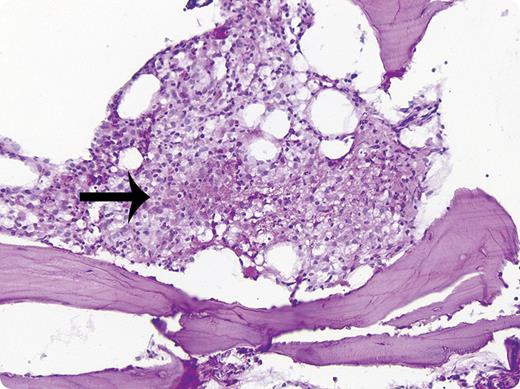

A 28-year-old black man was admitted to Presbyterian Hospital of Pittsburgh, PA, in August of 1959 with fever, hepatomegaly, and pulmonary infiltrates. Tuberculosis was suspected but the sputum examination was negative for acid fast bacilli. Needle biopsy of the posterior iliac crest (Westerman-Jensen needle) revealed granulomas (see figure) and the culture was positive for Mycobacterium tuberculosis. This prompted the initiation of isoniazid, steroids, and streptomycin. One week later a liver biopsy showed granulomas as well. After 5 weeks of therapy the patient had considerable improvement. A repeat bone marrow biopsy 7 weeks after the diagnosis showed no granulomas.

The biopsy in this patient was the first use of a needle biopsy for the diagnosis of systemic disease, a finding of historic and diagnostic importance. In the subsequent 53 years, the needle marrow biopsy has become routine for hematologists and oncologists to obtain additional information on systemic disorders such as metastatic neoplasms, staging of lymphomas, estimation of bone marrow cellularity, fibrosis, and iron stores, and for evaluation of metabolic bone diseases.